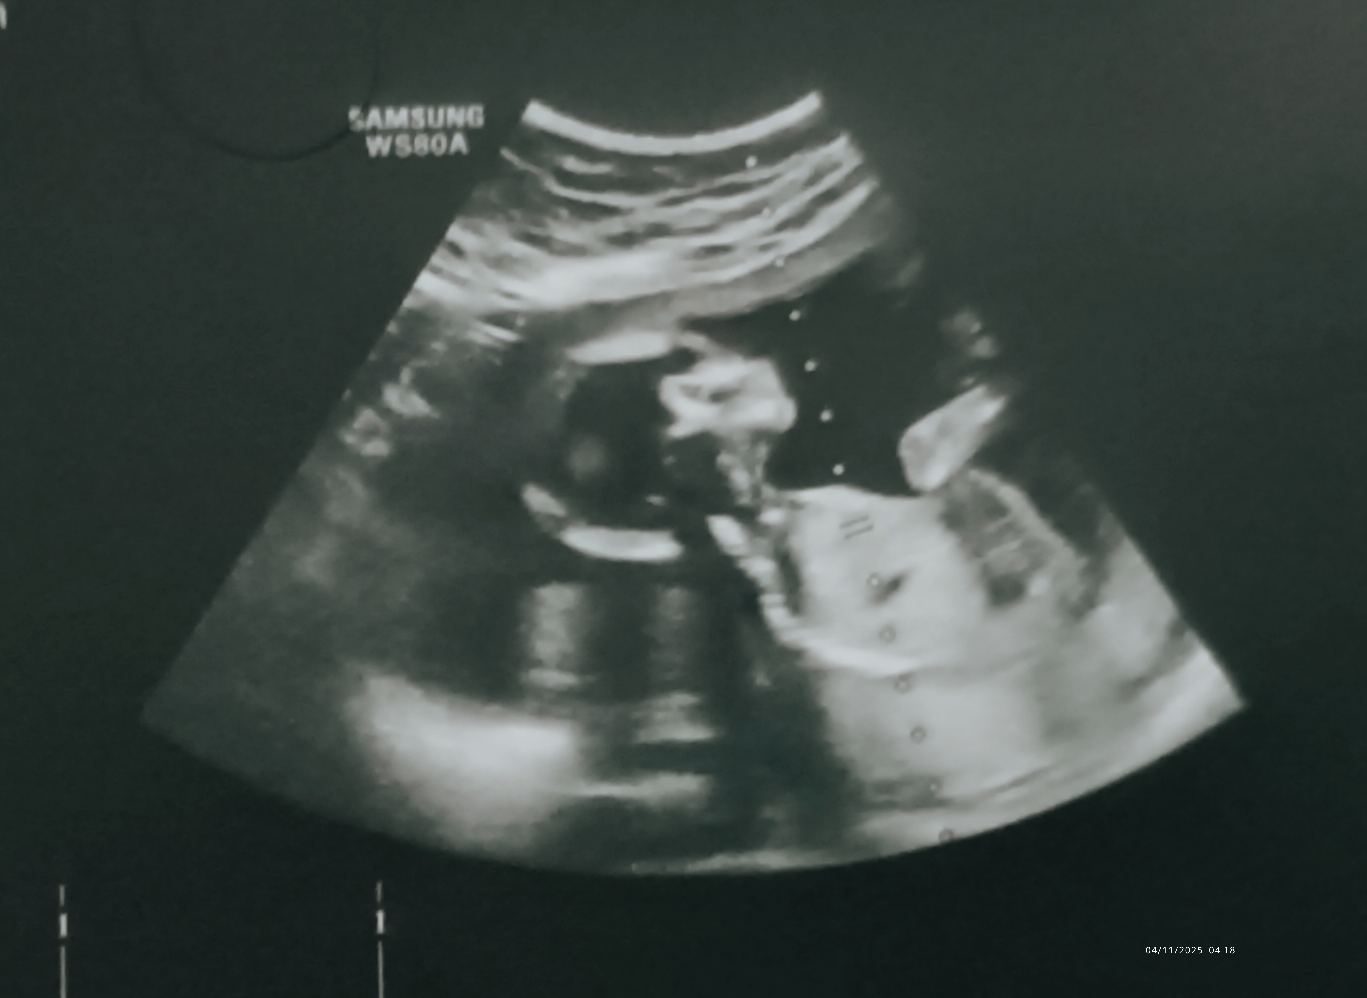

راستش خودمم فک نمی‌کردم نتیجش این بشه و نی نی کوچولوی ما دخترههه🎉🤭

اسمشم هانا ست💖به معنی نعمت و زیبایی